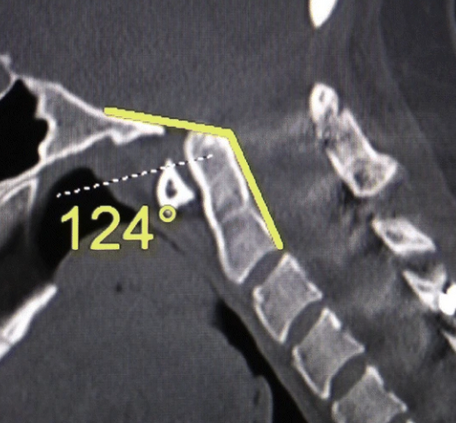

Image Type Cervical Spine X-Ray CT Scan MRI Scan Atlantodental Interval (ADI) Basion–Axial Interval (BAI) Basion–Dens Interval (BDI) Canal Occupying Ratio (COR) Clivo-Axial Angle Facet Joint Overlap (Percent Overlap Method) Facet Joint Step-Off/Dislocation Grabb-Oakes Measurement (pB - C2 line) Occipital Condyle–C1 Interval (CCI) Posterior Atlantodental Interval (PADI) Power’s Ratio Sagittal Vertical Axis (SVA) Segmental Angle Translation on Sagittal Reconstruction